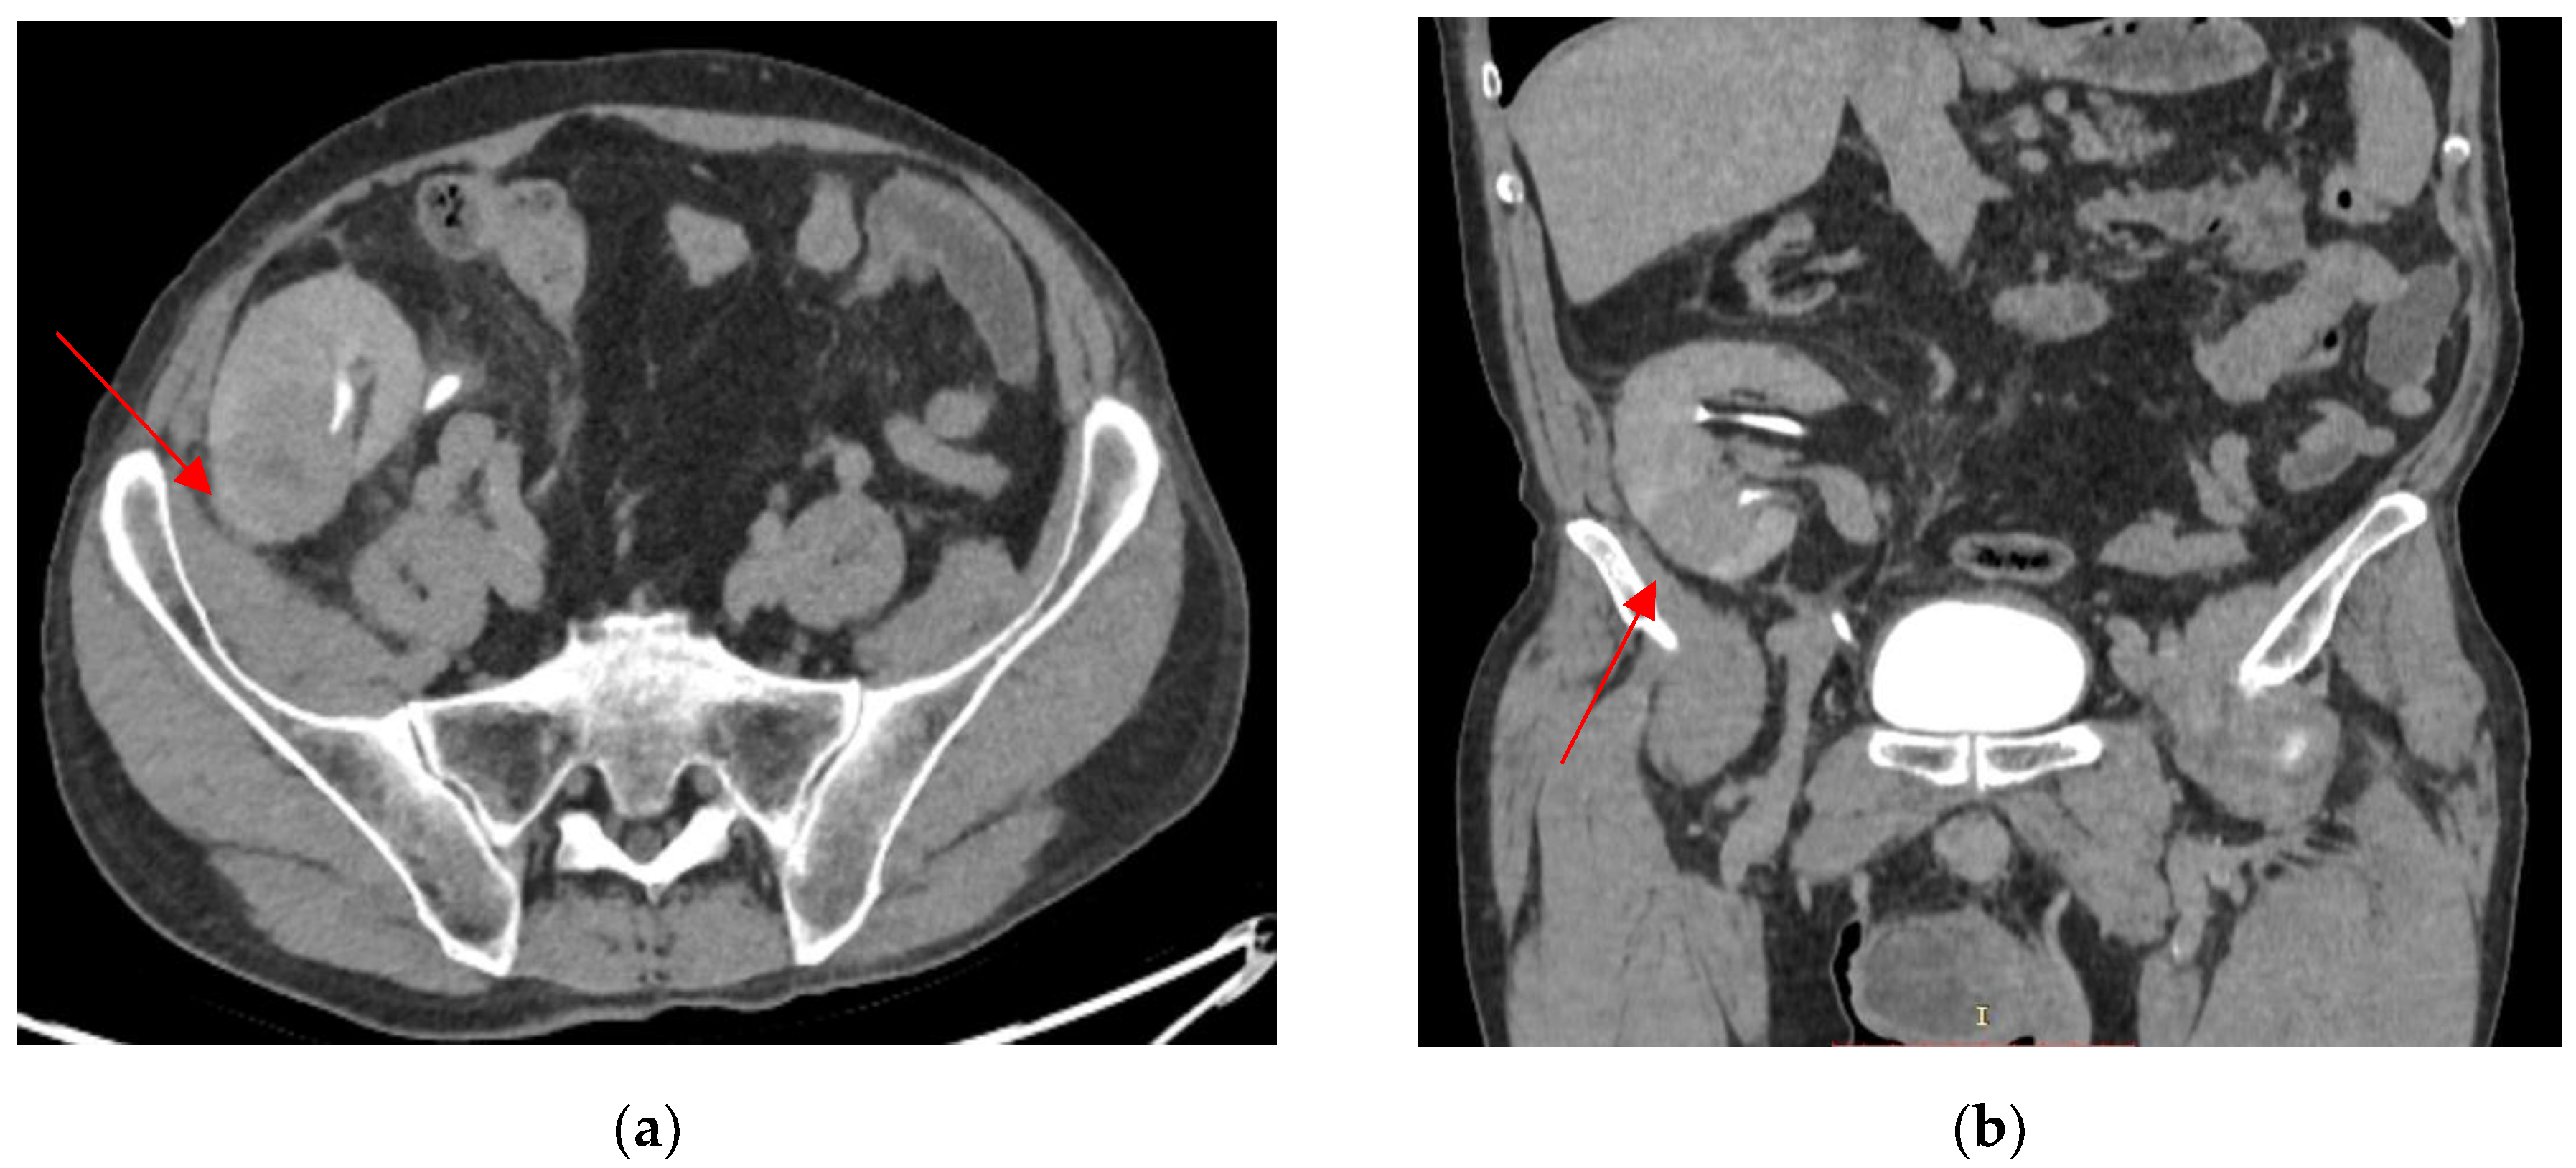

2. Case Presentation